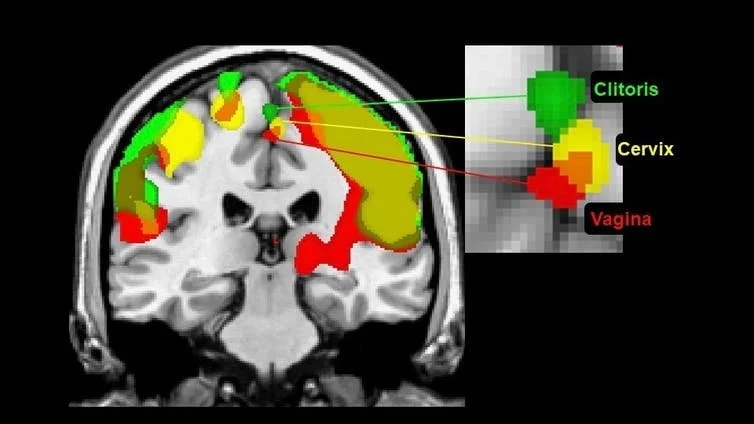

I love this graphic because it shows the innervation of the reproductive organs and how they connect to the brain.

Thanks to the work of Barry Komisaruk, PhD, we now have a representation of the genitals in the sensory cortex in people with uteruses. Until his research was published in 2012, we could only rely on the original map of the representation of the genitals in the sensory cortex “in humans” -- which was only tested in cis men. [1] You’ll find that research that was tested only in cis men is commonly used to represent all human beings, a travesty in many ways. The study used functional MRI technology to measure stimulation from different parts of the body, like the cervix, vagina, clitoris, and nipples.

• The clitoris, cervix, and vagina send nerve impulses to the same area in the remedial paracentral lobule of the brain, at the top of the head between the two halves of the brain

• The sensory cortical regions activated by each of the three genital regions are “to some extent separable and distinct”

• These findings are evidence that vaginal and cervical stimulation is NOT just an indirect stimulation of the clitoris, but that these areas have distinct sensory projections